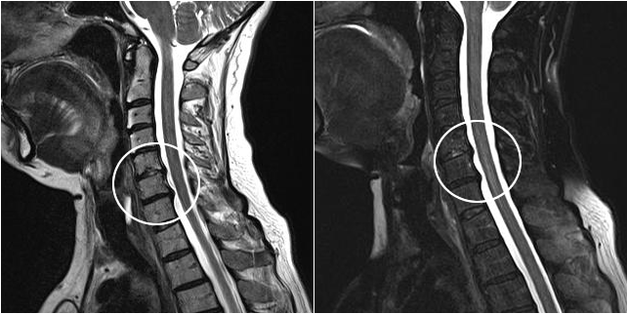

Modern diagnostic methods include MRI and CT, which make it possible to study the process of cartilage and bone destruction most accurately.Also, using this technique, it is easy to diagnose hernias and other soft tissue defects near the source of the disease.